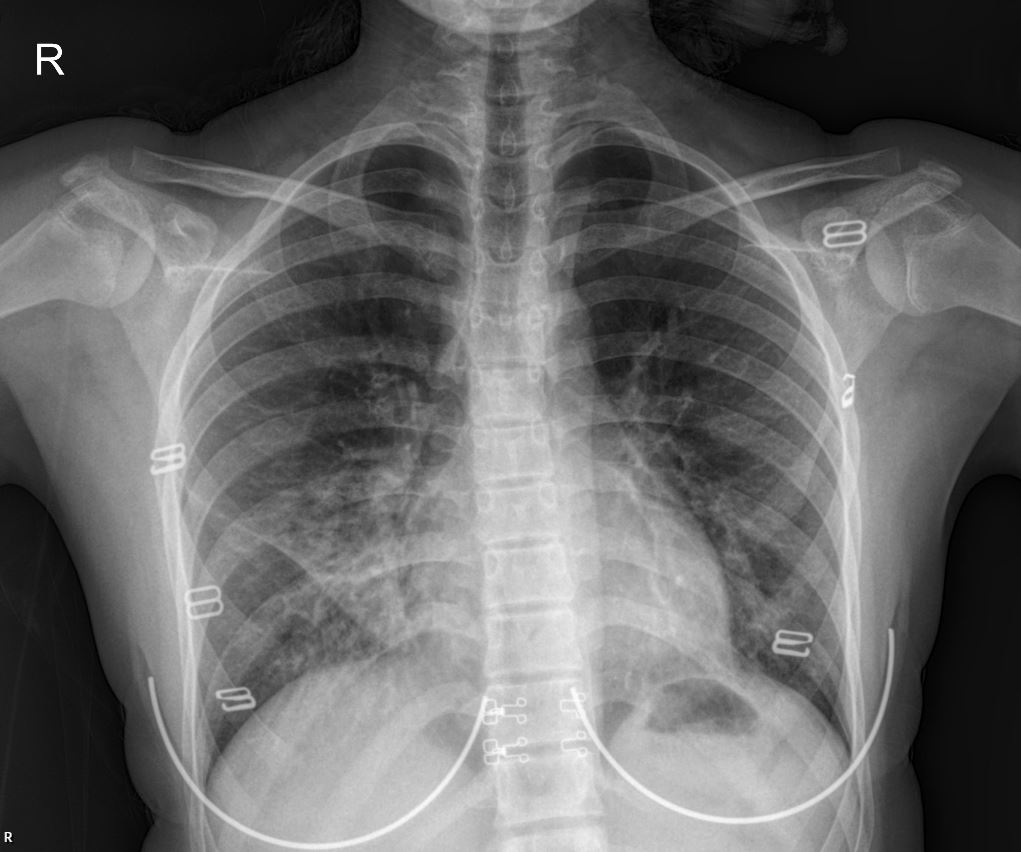

Given the patient’s symptoms and initial physical findings, a chest X-ray and subsequent CT scan were performed.

- PA Chest X-ray Interpretation: The initial PA chest X-ray (as shown above) revealed lobar involvement, indicating significant parenchymal changes consistent with an acute inflammatory process. The infiltrates are diffuse, particularly noticeable in the bilateral lower and mid lung fields, suggesting widespread involvement.

This case underscores the critical importance of investigating the underlying causes of recurrent respiratory symptoms in pediatric patients, especially when initial treatments provide only temporary relief. The combination of clinical presentation, chest X-ray findings showing lobar involvement, and CT scan results indicating peribronchial infiltration and ground-glass opacities points towards a complex respiratory pathology, potentially infectious or inflammatory. The history of frequent nebulizer use and hospital admissions highlights the need for a comprehensive diagnostic workup to identify any contributing factors, such as allergies, asthma, or immune deficiencies.